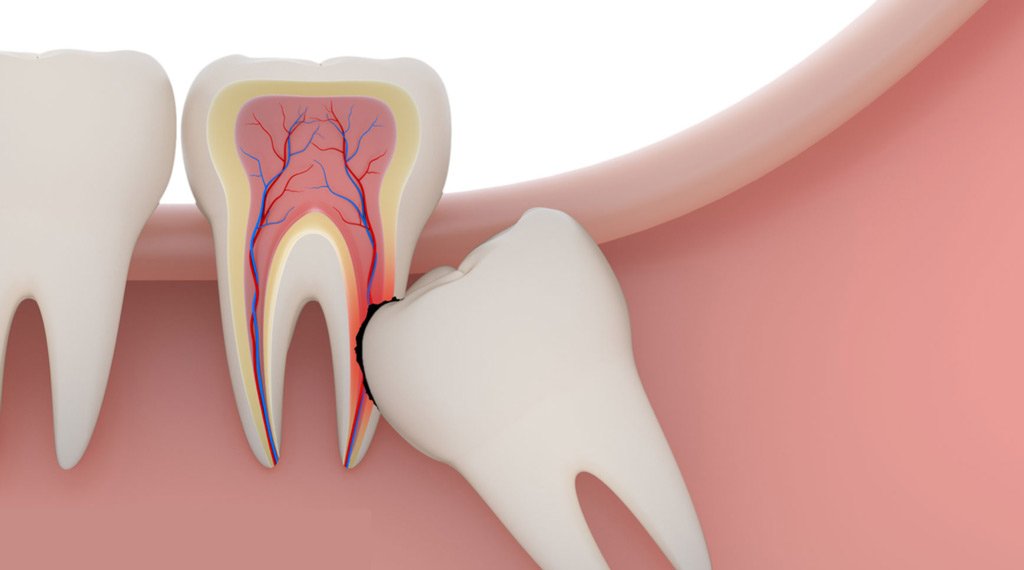

• Wisdom Tooth Extraction: This common procedure involves removing the third molars (wisdom teeth) which can cause pain, overcrowding, or infection if they don't erupt properly.